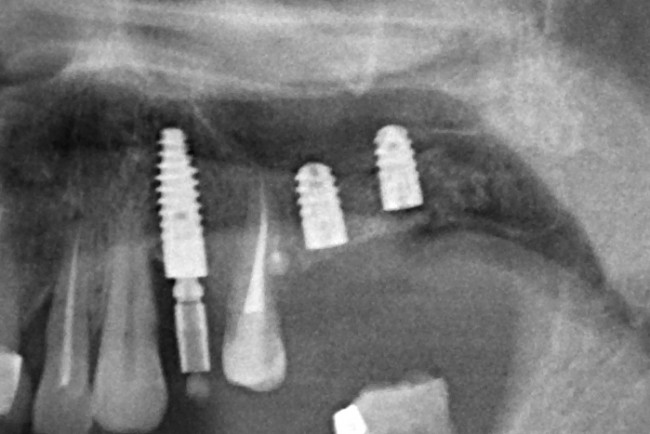

Вот снимок сразу после операции:

Мы делаем контрольный снимок.

Что на нем можно увидеть? Ничего. Для многих это будет открытием, но определить интеграцию/отторжение имплантов по рентгеновским снимкам возможно только в очень запущенных случаях. Мы можем лишь приблизительно сказать, что с графтом-регенератом все в порядке и остеопластика, можно сказать, удалась.

Важным условием гарантийных обязательств в нашей клинике являются профилактические осмотры, которые проводятся один или два раза в год (см. Гарантии и Долгосрочное наблюдение). Через полтора года после протезирования, при очередном осмотре мы сделали фотографии и снимок:

ортопантомограмма:

Сравните это с тем, что было раньше: